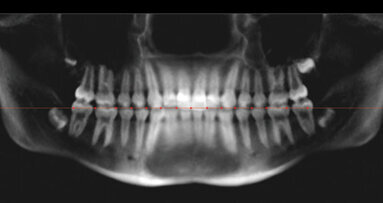

MIAMI, FL, USA: The principal oral care researcher worldwide for Procter&Gamble, Dr Robert Gerlach, gave a conference at the IADR 87th Session in Miami titled ‘Use of Gingivitis Image Analysis in a Randomized Controlled Trial,’ that proposes a new approach for measuring the efficacy of clinical trials.

“What we tried to do,” said Dr Gerlach, “was to bring objective measurements into clinical trials in oral care, using diagnostics, photography and other technologies, so our research can be conducted without bias, more efficiently, and bring out new products into the marketplace faster to meet the needs of patients.”

Dr Gerlach introduced a new technique to measure gingivitis “which is a very interesting disease for me, because is the one disease that every patient around the world has, has had or will have. The other interesting thing about gingivitis is that it is the oral disease where the symptoms and the clinical signs we see are the same.”

The researcher pointed out that the patient sees bleeding and that the bleeding can be measured for research purposes. He added that gingivitis is also a disease that the patient is aware of.

Dr Gerlach pointed as an example that if you have dental caries early, you never know it until you have cavitation and then you are at the restoration stage, but that gingivitis on the other hand can be treated and reversed.

“We are using simple photography to measure the color of gum tissue,” Dr Gerlach explained, “so this can be done any place in the world with simple equipment. We then extract the color from the photographs so we can measure color in the gingivae overtime because as there is less gingivitis color becomes pinker and tissue firmer, and we can measure color changes and compare it to other therapies.”

Dr Gerlach said this represents a real advantage compared with other conventional measurement methods. “The other important thing is that we can display the results to the individual or to a group of people, so they can see what will happen if they use dental floss or brush with rotational oscillational tooth brushes or an antimicrobial dental freshener or mouth rinse,” he said. “It allows us a great tool for dental education.”

Asked it patients will be convinced to floss more often or use the latest generation of electric brushes, Dr Gerlach said that patients and professionals like to see the results in people’s mouths.

“What we can do with this new technology is to photograph gingivitis and display it to the patient so hopefully it will increase its acceptability” of proven techniques to reverse it, said the scientist.

Dr Gerlach also cited at the IADR meeting the results of three studies conducted in Latin America by P&G, specifically in Guatemala. “The development of our new technologies is largely based on research conducted in Latin American populations,” he said. Two of the researchers involved in P&G investigations in Latin America are Luis Archila from the University of Texas Health Science Center at San Antonio, TX, USA, and Axel Popol, President of the Guatemala Dental College.